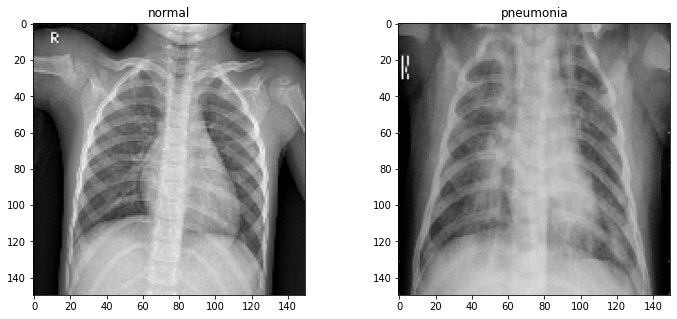

One of the simplest places to start is image classification. In this post, we will be looking at the methods and tools used to classify X-Ray images into one of two categories: normal or pneumonia.

All of the XRays have been scaled so that they're all 150 by 150 pixels in size. We can verify this by viewing a random pair:

fig, axs = plt.subplots(1, 2, figsize=(12, 5)) for ax, label in zip(axs, classes): ax.imshow(train[label][3], cmap='gray') ax.set_title(label) plt.show()